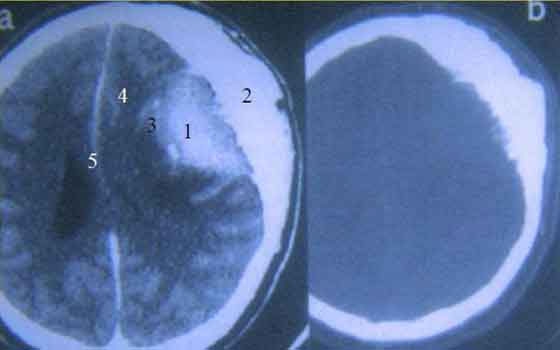

في بادئ الأمر عزا المختصون هذه الحالة الفريدة إلى "اضطراب سلوكي"، ليتبين لاحقا وبعد فحوصات متواصلة أن السر الضحك الذي يبدو من غير سبب يكمن في ورم وراثي حميد في دماغ الطفلة، يضغط على أجزاء معينة في المخ مما يؤدي إلى الضحك.

بعد التحقق من السبب خضعت الطفة لعملية جراحية تعافت منها بشكل تام، واستعادت قدرتها على الضحك بشكل طبيعي كغيرها. حول هذه العملية يقول الجراح الذي اشرف عليها سولومون موش إنها لم تكن ممكنة قبل 10 سنوات، لكن التطور العلمي والتكنولوجي سمح بإجرائها وبنجاح.

أما عن الحالة المرضية بحذ اتها فيقول موش إنها إحدى حالات الصرع النادرة، وأن الطفل الذي يعاني بسببها لا يشعر بالسعدة حين يضحك، بل على العكس إذ أنه يشعر بالخوف، مشيرا إلى أن بعض المصابين بهذا النوع من الصرع يعانون من نوبات البكاء.